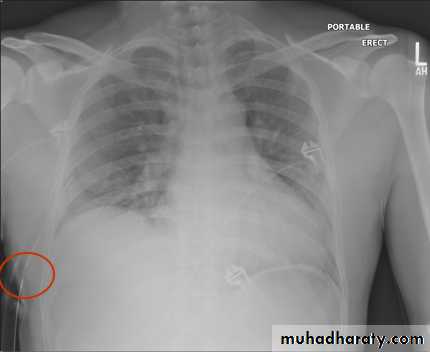

Severe dyspnea with shock

Tension PneumothoraxTension Pneumothorax

Area of hypertranslucensy (pneumothorax)

What is the difference?

(emphysematous bullae) (pneumothorax)